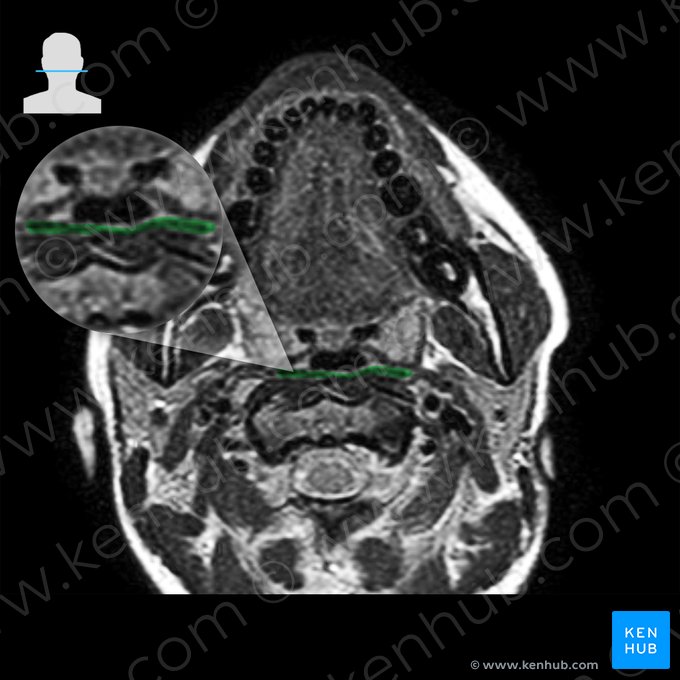

Músculo Constritor Médio da Faringe

O músculo se origina proximalmente do ligamento estilo-hióideo e dos cornos maior e menor do osso hioide. Ele se insere distalmente na rafe faríngea, da mesma forma que o músculo constrictor inferior da faringe. Ele realiza a constricção da parte média da faringe.